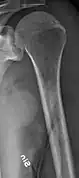

-

X-ray of the forearm, with lytic lesions -

Skull X-ray showing multiple lucencies due to multiple myeloma -

Multiple myeloma in the upper arm -

Pathological fracture of the lumbar spine due to multiple myeloma -

A CT of the brain revealed a lytic lesion in the left temporal bone (right side of image), and petrous temporal bones involving the mastoid segment of the facial nerve canal. Red arrows: lesion; green arrow: normal contralateral facial nerve canal. The lesions are consistent with a myeloma deposit.

Humerus with multiple myeloma lesions -

Same humerus before, with just subtle lesions